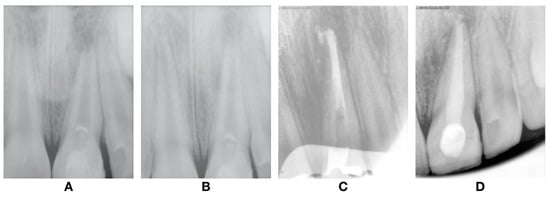

An eight-year-old male patient presented to the pediatric department at Egas Moniz Dental Clinic, Almada Portugal for an emergency appointment 30 days after orofacial trauma. The patient had no significant medical history to report. In clinical evaluation, extraoral examination showed no facial asymmetry or swelling. Intraoral examination showed an uncomplicated crown fracture (enamel and dentin) of the upper left central incisor (21) without fistula, and soft tissue laceration or alveolar bone fracture (Figure 1). In the diagnostic test, the tooth did not show any response to the different pulp test. The radiographic examination revealed incomplete root development and absence of periapical lesion (Figure 2). Taking clinical and radiographic findings into account, the concluded diagnosis was pulp necrosis.

Figure 2.

Preoperative orthopantomography.

At one-year follow-up, clinical examination revealed no signs or symptoms of pulp injury and the soft tissues were healthy. Radiographic examination revealed no signs of dentine wall thickening or continuous root development (Figure 5A). In the two-year follow-up, the radiograph revealed evidence that there was no sign of root development and apical closure as well as dentine wall thickening (Figure 5B). Thereby, and taking the radiographic images in the last two-year findings into account, we concluded that the revascularization failed, and an alternative endodontic treatment had to be accomplished. At this stage, the treatment options presented were: (1) new attempt of the REP; (2) apexification with MTA; or (3) apexification with the Ca(OH)2 procedure. The apexification with MTA was the elected treatment and was performed over two visits.

Figure 5.

Follow-up radiographs after revascularization. (A) 1-year follow-up; (B) 4-year follow-up; and after (C) plug MTA; and (D) root canal obturation.